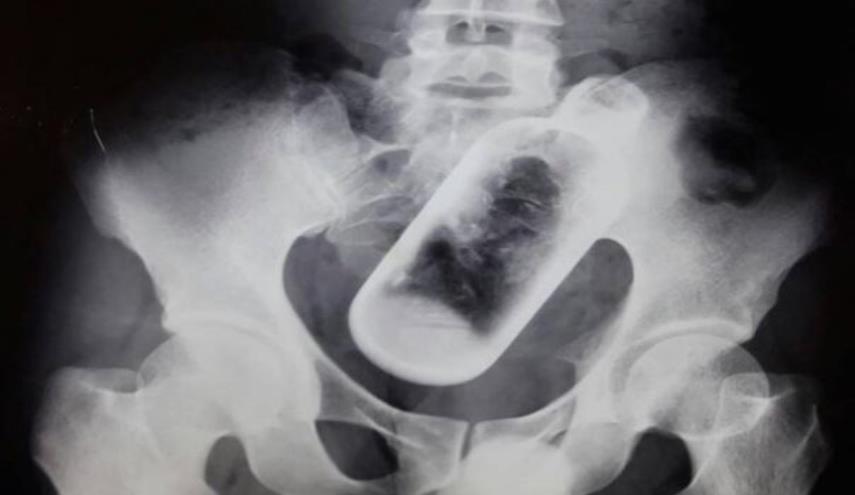

شاهد رجل عاني من آلام في المعدة وأسفل الظهر.. وعندما قرر تلقي العلاج كانت الصاعقة!

عاني رجل هندي، يبلغ من العمر 36 عاماً، من آلام حادة في معدته وأسفل ظهره، ليقرر الذهاب إلى الطبيب ويكتشف المفاجأة.